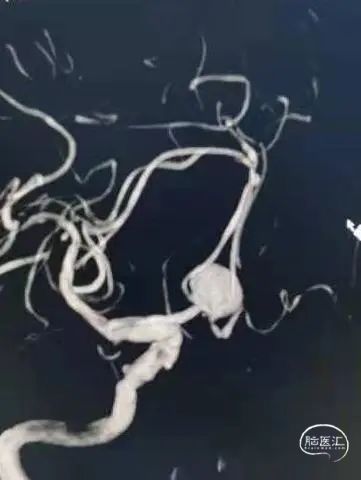

DSA结果:造影发现前交通动脉瘤,3D成像测量直径12mm,载瘤动脉直径1.85mm

术前3D-DSA造影:测量动脉瘤直径在12mm,载瘤动脉直径1.85mm。